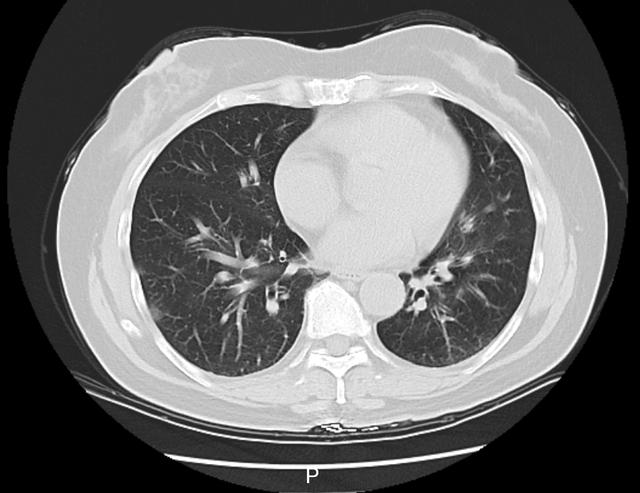

接诊的庞医生了解到,李阿姨在当地接受了一些治疗,但体温仍居高不下。家中同行的6个人,有5个人都先后发烧了。庞医生判断,李阿姨大概率是得了传染性较强的呼吸道疾病,立即给她安排了血常规、相关病毒抗原检测,以及更清晰的肺部CT检查,以便进一步了解病情。

李阿姨肺部CT影像

检测结果显示,李阿姨已经得了病毒性肺炎,甲型流感病毒核酸呈阳性。这一下,罪魁祸首找到了,是甲流搞砸了这一家人一次本该圆满的旅行。